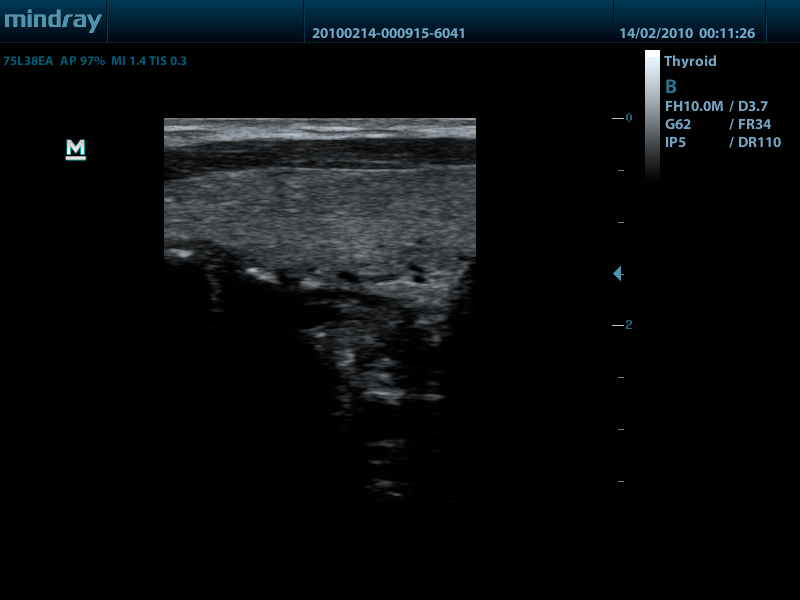

- Линейный датчик 75L38EA, 3.3 - 13.0 МГц, апертура 38 мм